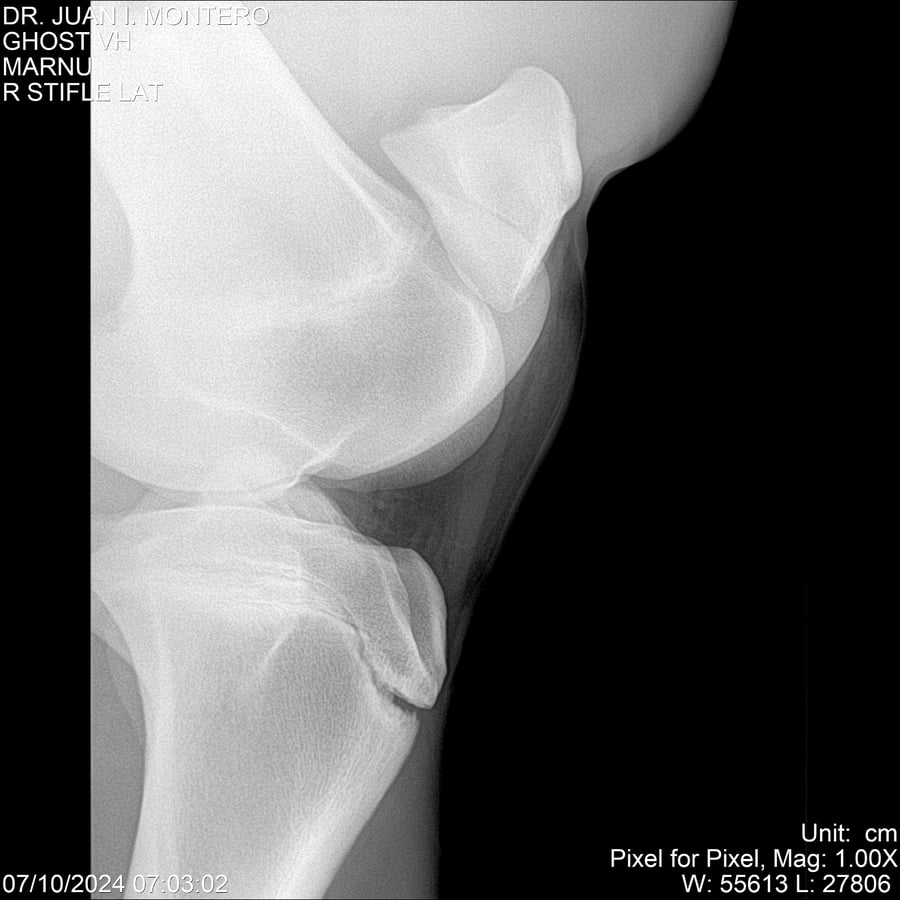

LOTE 15, GHOST VH 🔥 🔥 🔥 Lote Anterior Volver al remate Lote Siguiente Ficha Contacto Montevideo - Ficha del Lote Identificador: #282525 Categoría: Yeguarizos Montevideo - 69 Visualizaciones ClicData Contacto Empresa: Abelenda N. R., Walter Hugo Nombre*: Teléfono* : E-mail* : Mensaje Enviar Registrese gratis Este contenido Exclusivo está disponible sólo para usuarios registrados Ingresar